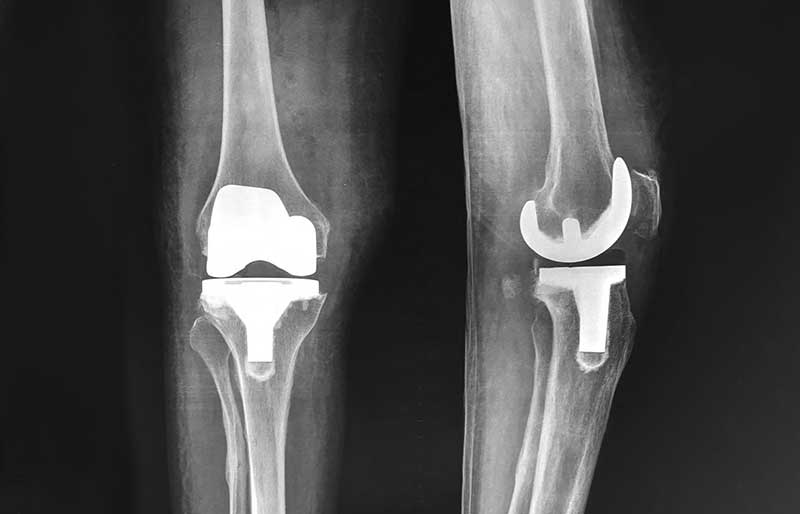

Operasi penggantian sendi lutut adalah suatu operasi untuk mengganti sendi lutut yang rusak akibat osteoartritis (penipisan tulang rawan) dengan sendi buatan yang disebut prosthesis. Penyebab utama kerusakan sendi lutut adalah osteoartritis (baca pen- jelasan tentang “Osteoartritis”) dan sendi yang paling sering terserang osteoartritis adalah lutut.

Operasi penggantian sendi lutut merupakan pengobatan terbaik untuk osteoartritis lutut stadium 3 dan 4. Ada empat tujuan operasi ini, yaitu menghilangkan rasa sakit sendi yang telah rusak, memperbaiki lingkup gerak sendi yang sebelumnya kaku dan terbatas, mengembalikan kemampuan penderita melakukan aktivitas harian tanpa rasa sakit, dan meningkatkan kualitas hidup sehingga penderita kerusakkan sendi dapat menjalani hidup secara aktif bebas dari nyeri sendi.

Operasi penggantian sendi lutut biasanya berlangsung sekitar 2 jam. Sama seperti operasi yang lain, di jaman modern ini operasi penggantian sendi lutut merupakan operasi yang aman bagi orang tua (pada kenyataannya, sebagian besar penderita osteoartritis sendi lutut adalah para orang tua!). Dengan kemajuan teknologi dan ilmu kedokteran modern, operasi penggantian sendi lutut aman bagi orang tua yang biasanya juga menderita kencing manis, penyakit jantung dan tekanan darah tinggi.